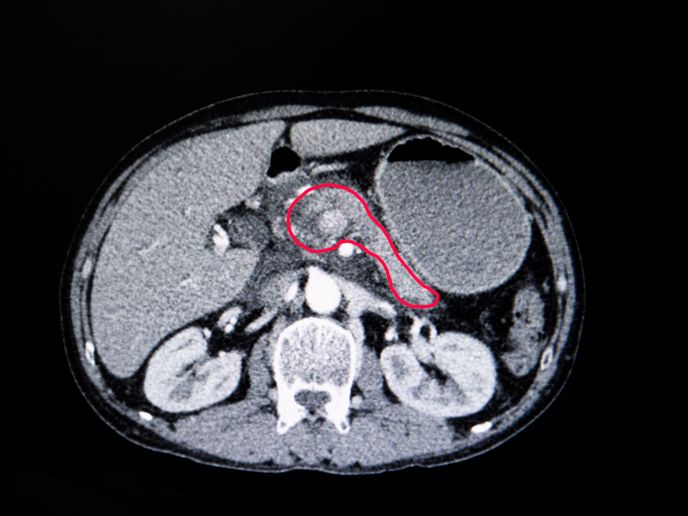

La resistenza ai farmaci antitumorali è un problema ampiamente diffuso. Secondo quanto rilevato da una recente scoperta che mette in connessione la farmacoresistenza, la recidiva della malattia e la morte nel carcinoma polmonare non a piccole cellule, esiste una variazione del numero di copie di regioni genomiche, sia all’interno delle cellule dello stesso tumore che nelle diverse regioni tumorali di un paziente. «All’interno di un tumore si verificano cambiamenti nel numero di copie, osservabili in ogni cellula», spiega Eva Grönroos, ricercatrice di laboratorio senior presso l’Istituto Francis Crick(si apre in una nuova finestra). «Il risultato è che non tutte le cellule all’interno del tumore sono caratterizzate da un numero di copie cromosomiche identico e che dispongono di un diverso corredo genetico», aggiunge l’esperta. Nell’ambito del progetto PROTEUS, finanziato dal Consiglio europeo della ricerca(si apre in una nuova finestra) (CER) e guidato dal docente Charles Swanton(si apre in una nuova finestra), i ricercatori hanno cercato di approfondire questa scoperta sviluppando modelli di cancro al polmone che potessero contribuire a svelare i modelli evolutivi alla base di tale instabilità genomica. «Una delle informazioni acquisite in questo progetto è che tali cambiamenti non sono completamente casuali(si apre in una nuova finestra) », afferma Grönroos. «Gli stessi guadagni e perdite vengono spesso osservati all’interno di uno specifico tipo di tumore, a indicare che le pressioni di selezione specifiche in base al tipo di cancro modellano il genoma tumorale.»